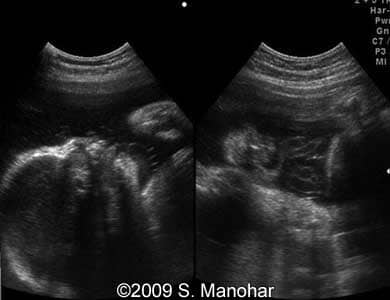

Images 8, 9, 10, 11, 12, and 13: The images shows discontinuities of the skin surface (arrows), a typical sign of the Harlequin type ichthyosis.

8-b

8

9-b

9

10-b

10